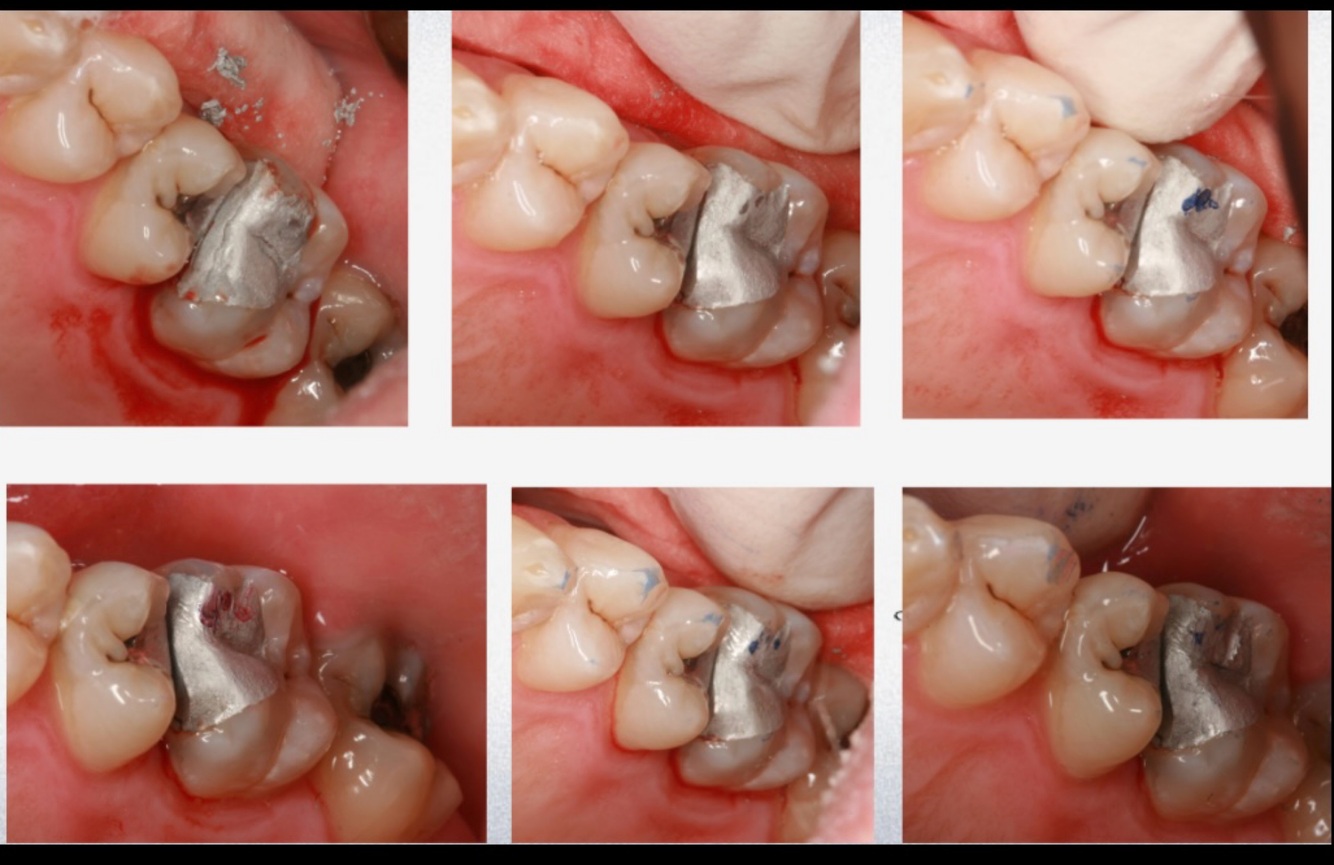

Q

This tooth (restored by amalgam) is:

15

27

14

16

A